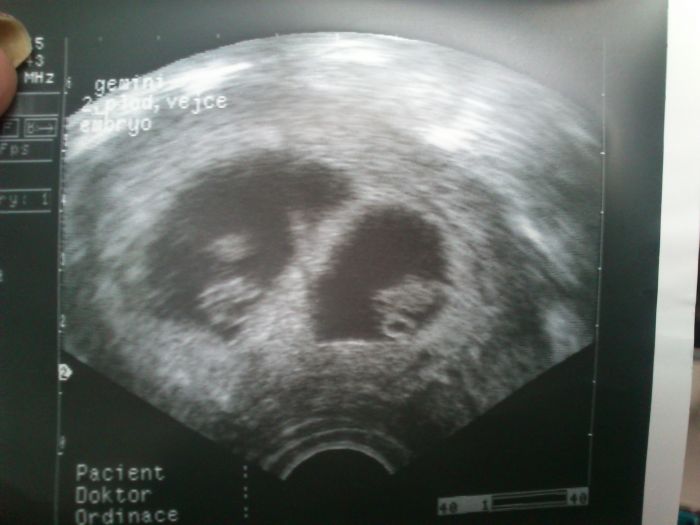

Tak krásného dne dámy přeji :0) Moc děkuji za držení palců- vyplatilo se :0))) Mám dneska pro toho svýho prima dárek- má svátek :) No dobře, tak už nenapínam - jsou to dvojčátka :0) jedno 7+5 druhé 7+6 - srdíčka jim buší jako o závod a všechno vypadá tak, jak má :0))))))))))))))))))))))) Neeeeskutečně se mi ulevilo, a přiznávám, že vnitřně jsem ráda, že to nejsou trojčata, z toho jsem fakt měla strach:0) Další kontrola 30. července :0) Jinak jsem dostala utrogestan pro sichr, tak snad všechno bude probíhat jako dosud ... Ještě jednou moc děkuji za držení palců :0))